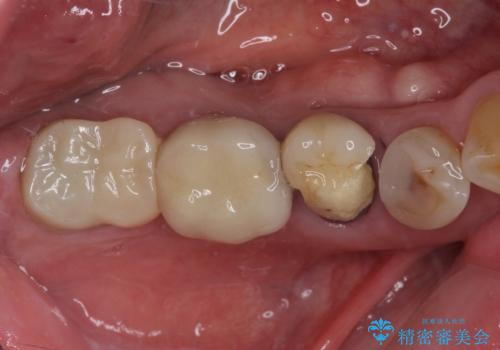

- 強い咬合力により表面のセラミックが剥がれ、裏打ちの金属が見えてしまっていることを気にして来院された患者様です。

仮歯に変えた後、咬合力に耐えることを目的に強化セラミッククラウンにて補綴することとしました。